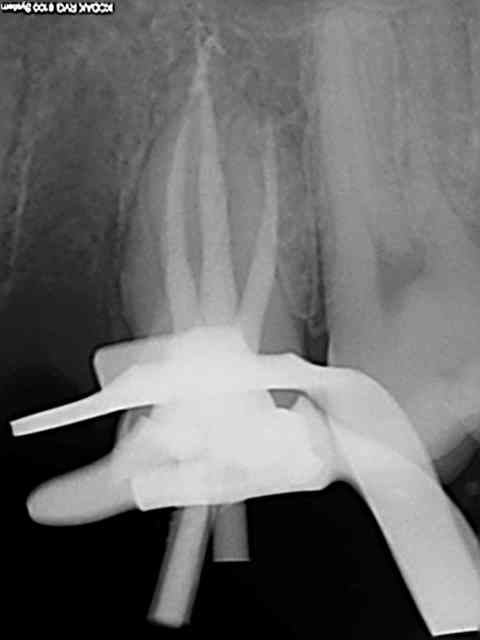

Je crois qu'effectivement la CAO peut être chiante, moi ça m'éclate. Il y a du boulot pour toutes les préférences et le travail de molinarius réunit le meilleur des deux mondes.

c'est du beau travail jumpingjack !

oui c'est du beau travail ..

Cependant je suis sure que ces types de cas ne se réalisent pas en deux temps trois mouvements!

il y du temps d'usinage , beaucoup de modelage pour parvenir à de tels cas et autant pour la finition .. donc on en revient toujours au même .. le temps que vous passez dessus vous ne le passez pas au fauteuil ...secu ou pas , votre rentabilité est ailleurs..

Sur le 1er cas de jump.... reconstitution au maxillaire , il y a plusieurs usinage(quelques heures) et un certain de temps finition à la pièce à main ... et sur d'autre plusieurs cuisson de maquillage sans doute ...

Que certains prats soient doués à jouer les prothésistes ;) c'est une chose mais je suis sure que c'est plus par plaisir de faire de la prothèse :) plutôt qu'un intérêt financier ... je me trompe jumpingjackflash ?